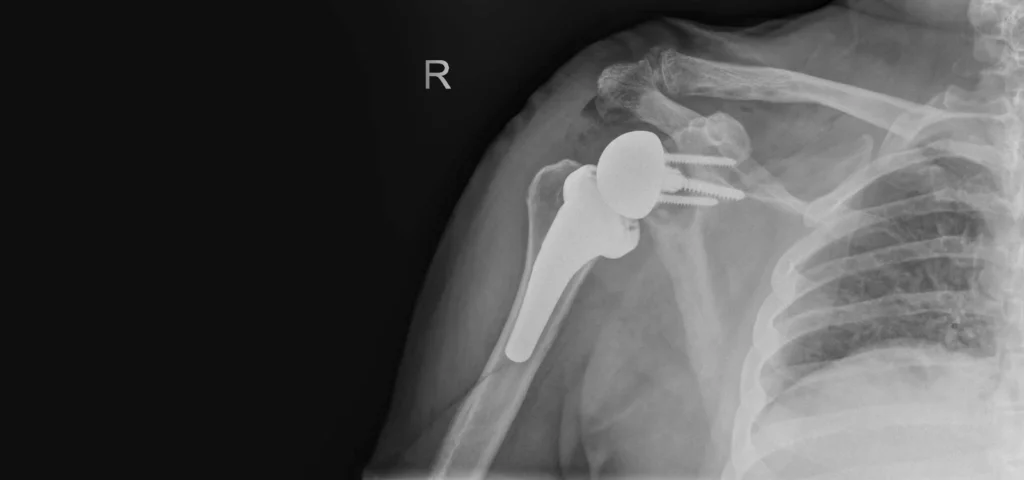

Ανάστροφη Αρθροπλαστική Ώμου

Η ανάστροφη αρθροπλαστική ώμου είναι ένας ειδικός τύπος χειρουργικής αντικατάστασης...